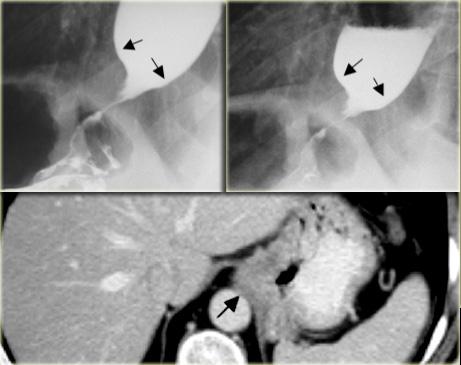

Hình bên trái là bệnh nhân không có triệu chứng với u cơ trơn thực quản.

Trên phim ngực thẳng, quan sát thấy một đám mờ bất thường phía sau tim (mũi tên).

Hình chụp thực quản cản quang barium cho thấy một khối có múi (mũi tên) không gây tắc nghẽn mặc dù kích thước lớn.

Trên phim X-quang, khối u (mũi tên) lồi vào ngách azygô-thực quản.

Trên hình chụp thực quản cản quang, bờ dưới của tổn thương trong thành này tạo thành góc gần vuông (mũi tên) với thành thực quản.

Một khối thực quản có vôi hóa hầu như luôn luôn là u cơ trơn.

Hình bên trái là bệnh nhân có tổn thương thực quản vôi hóa (mũi tên) lồi vào ngách azygô-thực quản trên phim X-quang.

Tổn thương (mũi tên) trên CT và phim X-quang bệnh phẩm phẫu thuật cho thấy hình ảnh vôi hóa.